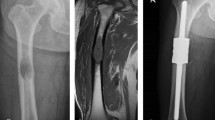

A retrospective analysis was conducted on a patient who underwent hemipelvic replacement at the Second Hospital of Jilin University, Changchun, China. The patient was a 73-year-old female who underwent left hemipelvic resection and artificial hemipelvic replacement due to left hip pain accompanied by restricted mobility. PET-CT results showed that left acetabular, pubic and ischial bones destruction and soft tissue mass, invading the lower part of the left femoral head neck, with increased metabolism, suggesting malignant tumor. Pathological results showed that thyroid follicular tissue was suspected to be metastatic thyroid follicular carcinoma. Immunohistochemical staining results showed CK (AE1/AE3) (+), ER (−), PR (−), Ki67 (positive rate 10%), PAX-8 (+), TTF-1 (+), TG (+), GATA3 (−). CT and MRI fusion images could be found in Supplementary material 1. And, this patient underwent thyroid lesion resection surgery four months ago. Six months after the operation, patient complained that there was no obvious cause leading to hip pain and a pelvic radiograph revealed loosening of the prosthesis and a broken screw (Fig. 1). During this period, the patient underwent thyroid tumor chemotherapy treatment. This study received approval from the Ethics Committee of the Second Hospital of Jilin University (SB [2021] No. 152). This participant was informed and signed informed consent forms.

Based on the preoperative design and postoperative thin-Sect. (0.625 mm) computed tomography (CT) scan imaging data, the patient’s pelvis and prosthetic structure were segmented using Mimics 19.0 software (Materialize, Belgium), and the model was subsequently imported into SolidWorks software (Dassault Systèmes) in STL format. Following this, the shape and contour of the hemipelvic prosthesis were refined, and the preliminary model was exported to Magics 19.0 software (Materialise Company, Belgium) for size adjustment, surface smoothing, and other modifications. Based on the observed operative conditions, four 6.5 mm diameter iliac locking screws (25 mm, 55 mm, 55 mm, and 50 mm) were surgically implanted. The integration of a 3D reconstruction model with postoperative imaging clearly demonstrates that the prosthetic reconstruction aligns well with the intended design (Fig. 1). The prosthesis was 3D printed and simulated for surgery, and bone-contact surface of the implant was designed with porous-coated (Supplementary material 2). Due to the controversy surrounding the fixation of the pubic, the connection of pubic and was not selected (Fig. 1).

Currently, the design process for 3D printed hemipelvic prostheses involves preoperative design, prosthesis verification, surgical planning, and other preparations before clinical application8,15. Prosthesis refinement requires referencing physical and chemical performance tests, as well as clinical follow-up results, to gradually improve the design, thereby enhancing the initial stability of the hemipelvic prosthesis. This study was prompted by the discovery of broken iliac screws in a patient after hemipelvic replacement in zones II + III (Fig. 1). To analyze the causes of screw breakage and offer a theoretical basis to design future hemipelvic prostheses, this study examined the stress and micromotion post-initial implantation and sought to enhance the prosthesis design.